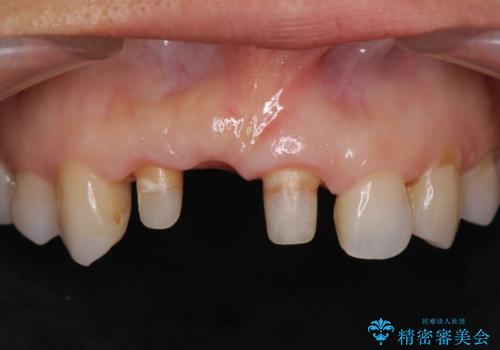

- 前歯のブリッジがすぐに外れる、歯ぐきが腫れている、見た目を良くしたい、と希望され来院されました。

現在装着されているブリッジを除去したところ、歯ぐきよりも上に存在する歯質(縁上歯質)が少なく、土台の形態の悪さや不適合などさまざまな問題があります。

根管治療を行ったのち、歯周外科を行うことで、欠損部の歯ぐきの厚みを出し、縁上歯質を獲得することで、長期的な予後の見込めるブリッジを製作できる環境を整備していきます。